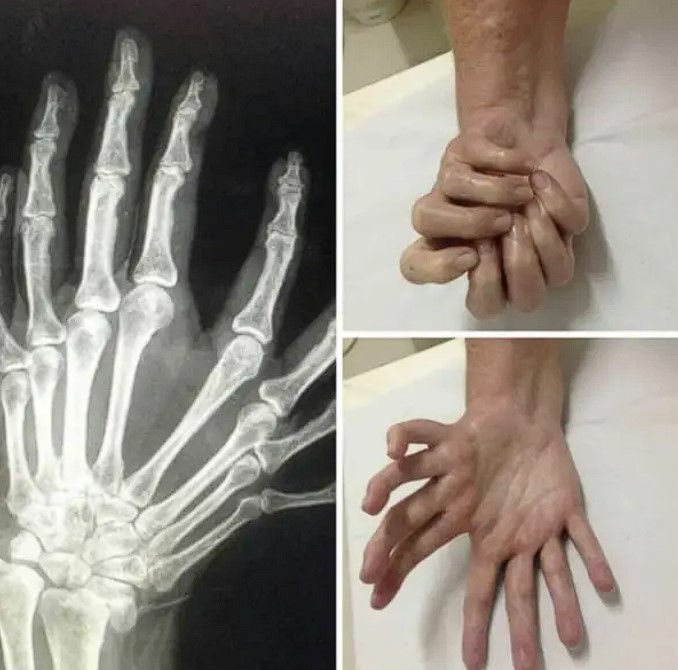

#8 Syndróm zrkadlovej ruky, pri ktorom máte dve ruky (mínus palce) v jednej